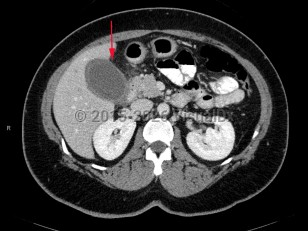

Acute cholecystitis is a surgical emergency of the biliary tract that can be life-threatening if appropriate treatment is not initiated promptly. Acute cholecystitis is characterized by gallbladder wall inflammation. Patients classically present with right upper quadrant (RUQ) abdominal pain, fever, and leukocytosis. Acute cholecystitis is further categorized by the presence of gallstones as calculous or acalculous.

Acute calculous cholecystitis occurs when a gallstone blocks the cystic duct, impairing gallbladder drainage. Temporary obstruction can cause biliary colic. Sustained obstruction can result in gallbladder dilation, wall inflammation, subsequent wall thickening, and pericholecystic fluid accumulation.